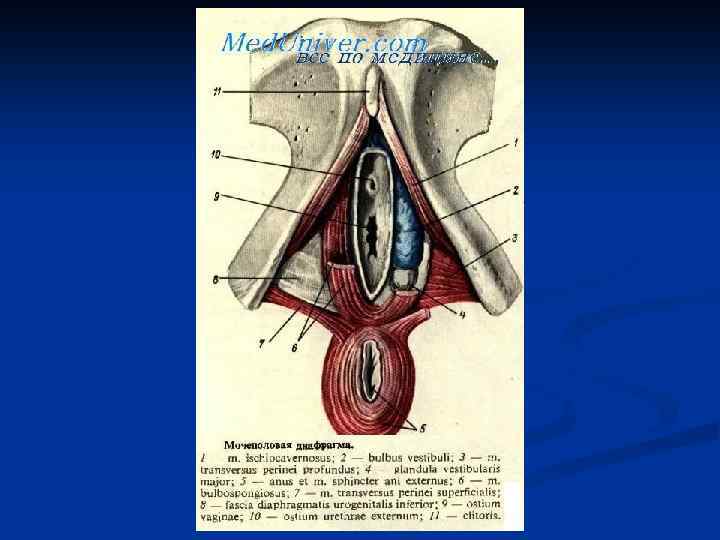

Женские половые органы, organa genitalia feminina

Женские половые органы, organa genitalia feminina